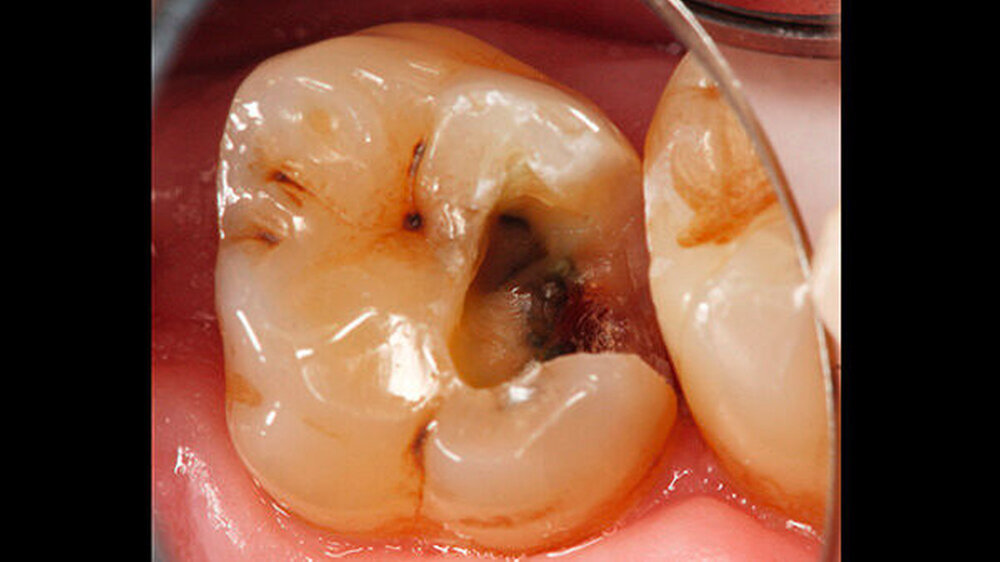

Ein 72-jähriger Patient stellte sich im Oktober 2013 zu einer Routinekontrolle in der Poliklinik für Zahnerhaltung und Parodontologie der Universität Regensburg vor. Bei der Befunderhebung wurde aufgrund des Verdachts auf Approximalkaries eine Röntgenaufnahme im Bereich des zweiten Quadranten angefertigt. Im Bereich des Zahns 26 distal wurde eine "Caries profunda“ diagnostiziert (Abbildung 1) und daher ein Termin zur Füllungstherapie vereinbart.

-Schnee war positiv. Die Behandlung wurde auf Wunsch des Patienten ohne Lokalanästhesie durchgeführt. Vor der Präparation erfolgte das Anlegen von Kofferdam an den Zähnen 24 bis 27. Zunächst wurde mit rotierenden Diamantschleifern unter Wasserkühlung von okklusal ein Zugang zum Defekt geschaffen. Der distale Kavitätenbereich wurde mit oszillierenden Instrumenten präpariert (SonicFlex, KaVo) (Abbildung 2). Dabei wurde die Kavität so zierlich wie möglich gestaltet.